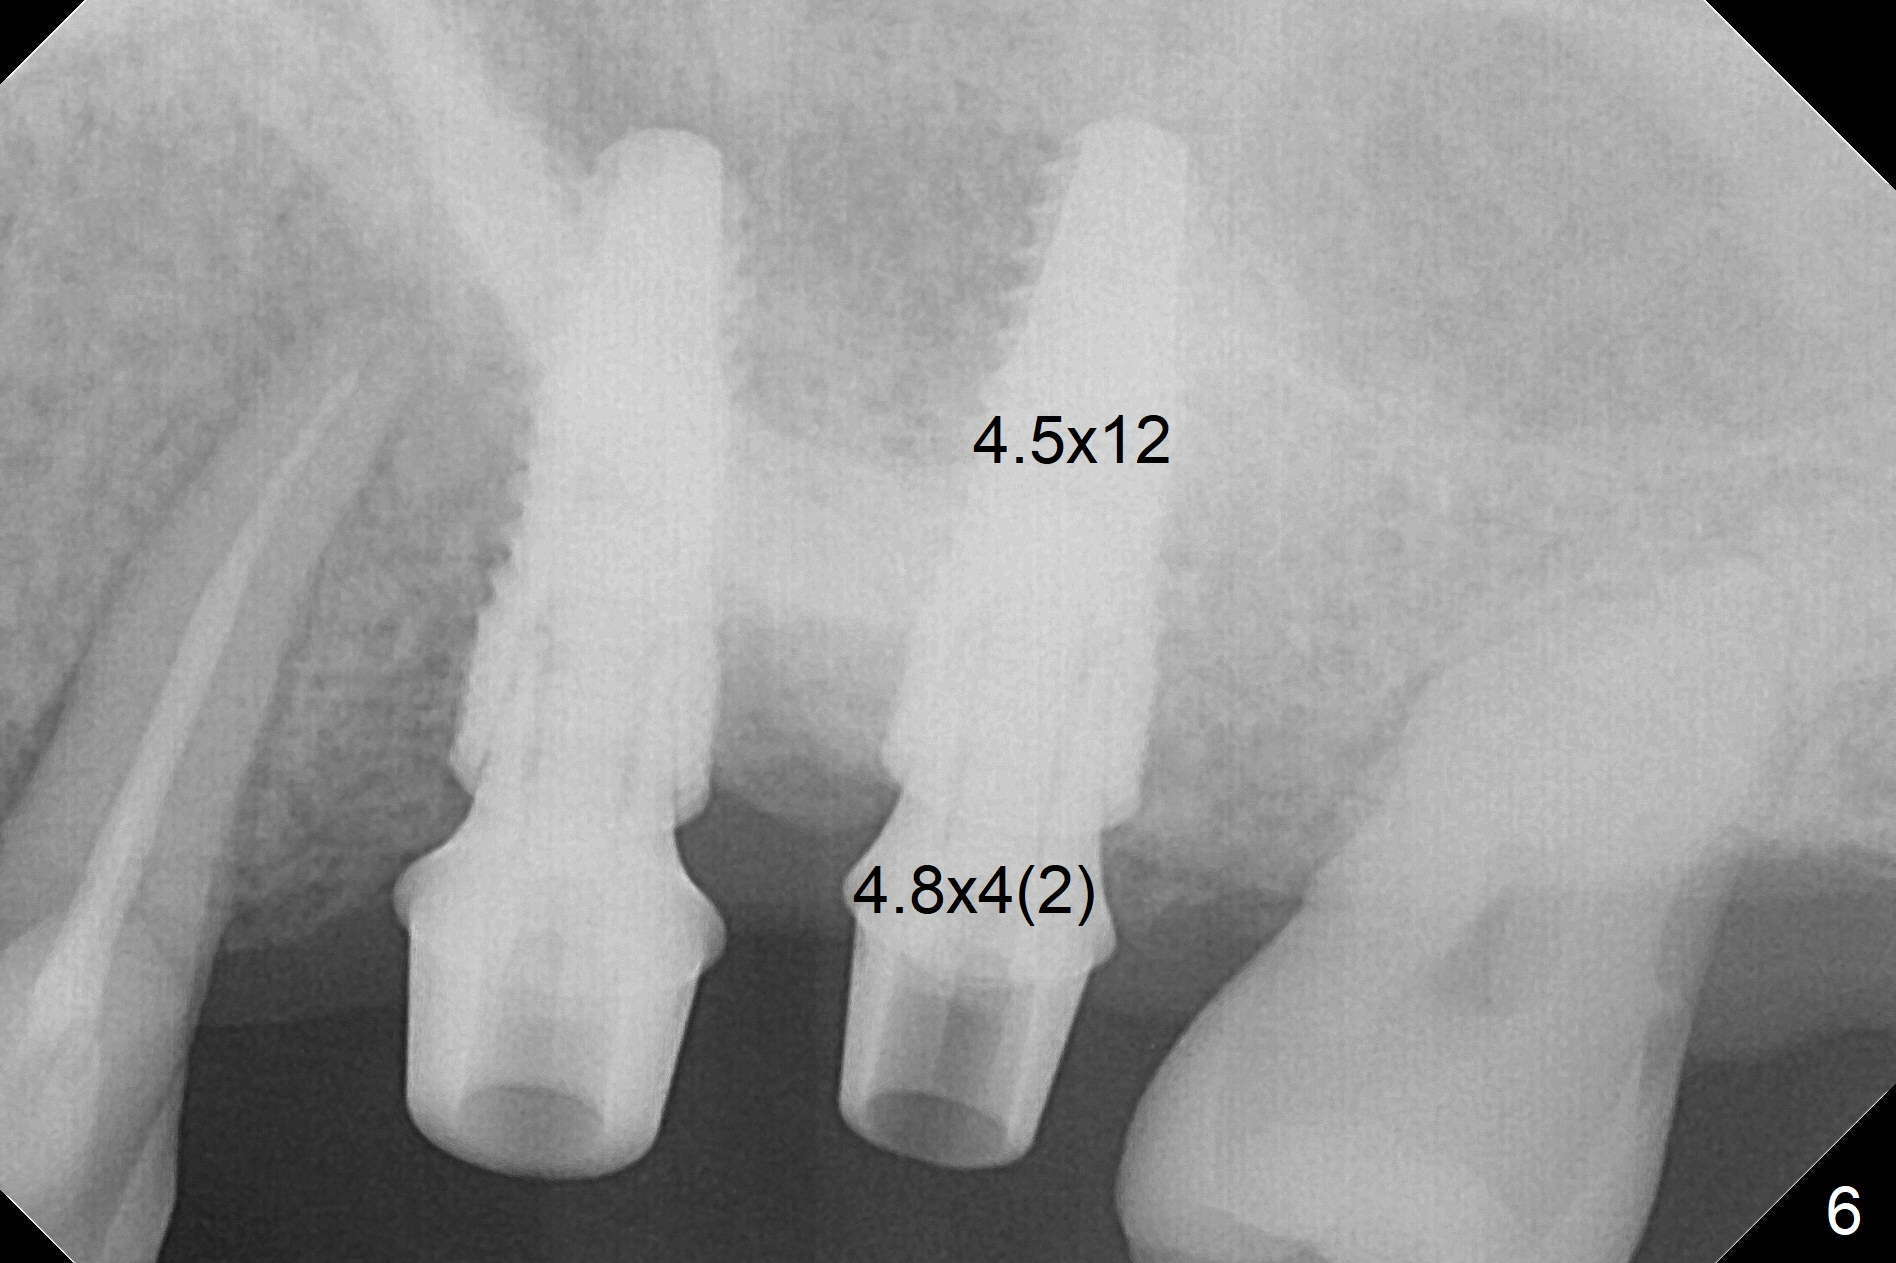

When 1.2 mm drill is used for osteotomy at #14 and 15, the bone feels to be soft (Fig.1). After change in trajectory (Fig.2), Expander 1 (Fig.3: E1, 1/1.6 mm) can be inserted at #14 and 15, while E2 (1.2/2.3 mm) cannot at full length at #14, suggesting hard bone. Osteotomy continues with drills until 4.1x14 mm, followed by insertion of E4 (2.4/3.7 mm) at #14, while osteotomy goes on until E3 (1.7/3.1 mm) at #15 (Fig.4). A 4.5x12 mm SM implant is placed with 50 Ncm (with insertion of a 5.8x4(2) mm abutment as a guide for #15 osteotomy, Fig.5). The apical portion of the osteotomy at #15 (Fig.5 red line) is finished with drills, leading to placement of a 4.5x12 mm implant (>50 Ncm) and 4.8x4(2) mm abutment (Fig.6). With bone density is more than 200 units, bone expansion appears to be not indicated. The patient returns for #13-15 crown prep 4.5 months postop (Fig.7). Abutments change to 5.8x5(3) and 5.8x4(3) mm at #14 and 15, respectively with mesial reduction of the tooth #16 (curved line) before impression. Minimal bone loss is observed 1 year 5 month post cementation (Fig.8,9), thanks to pre-existing wide bone.